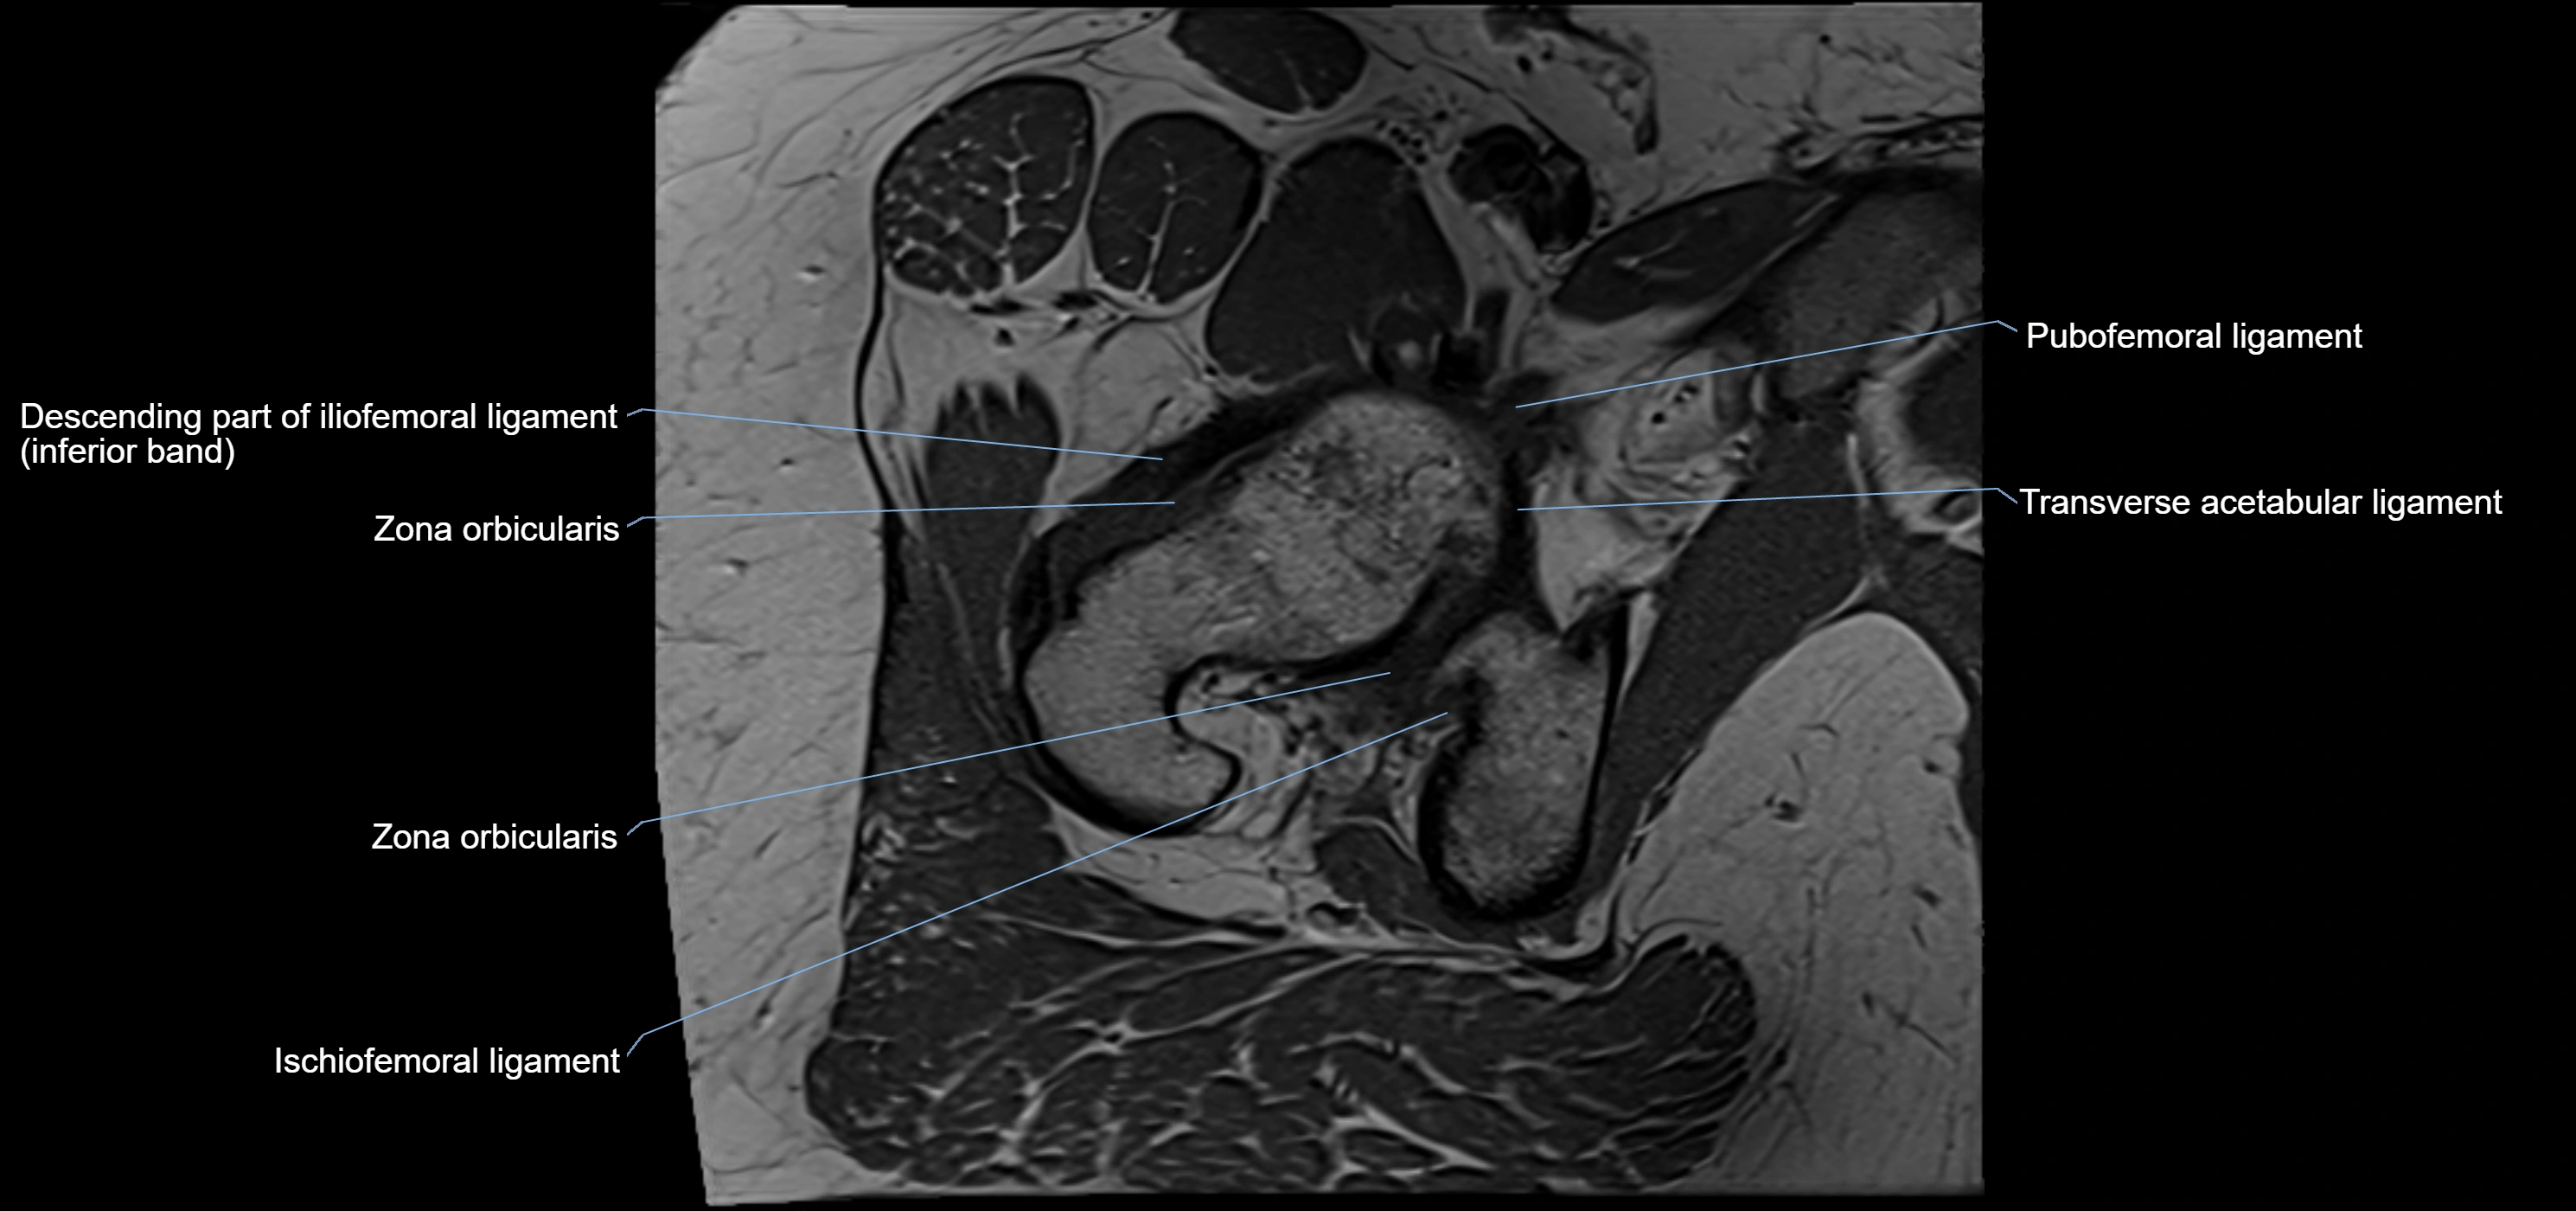

The acetabular labrum is a fibrocartilaginous ring that surrounds the rim of the acetabulum in the hip joint. It deepens the hip socket, increases joint stability, and maintains a suction seal that preserves negative intra-articular pressure. Structurally, the labrum transitions from hyaline cartilage of the acetabulum to dense fibrocartilage at its free edge.

It is triangular in cross-section, with its base attached to the acetabular rim and its apex projecting toward the femoral head. The labrum is most robust superiorly and anteriorly, where load bearing is greatest, and relatively thinner inferiorly.

Structure and Relations

• Superior and anterior labrum: thickest portions, stabilizing against anterior dislocation

• Inferior labrum: blends with the transverse acetabular ligament bridging the acetabular notch

MRI Appearance

T1-weighted images:

• Labrum: low signal intensity (dark)

• Surrounded by intermediate signal joint fluid (bright on arthrogram)

• Tears: linear or focal areas of intermediate-to-high signal interrupting labral continuity

T2-weighted images:

• Joint fluid: bright, making labral tears visible as fluid extending into or around labrum

• Degeneration: may show areas of increased signal within labrum